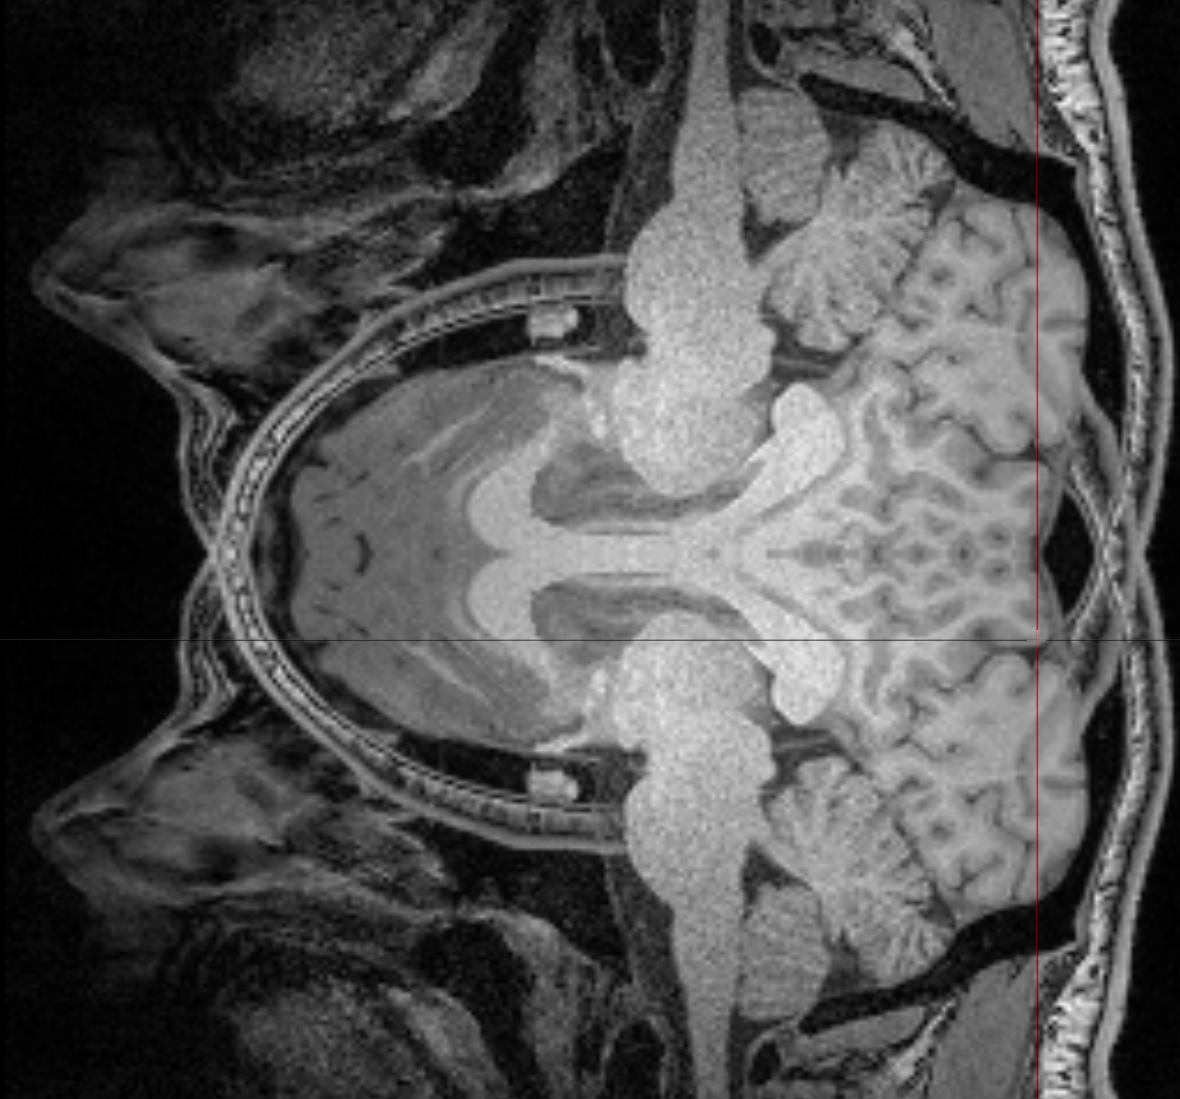

I am using a commercial software called 'Vivoquant' to view the data. I, however, tried your data on both SPM and MRIcroGL and for both instances, the images still appears to be flipped. I've attached a screen capture of the images viewed through MRIcroGL.

Regarding your concerns about the images being 3D, I've tested dcm2niix binary on both 3D (pre-clinical) and 2D (clinical) images and for both attempts, I get a flipped image on the same axis.